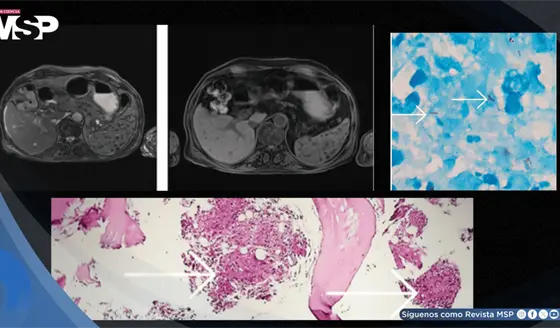

Pancitopenia por tuberculosis con compromiso de médula ósea en paciente con esteroides crónicos